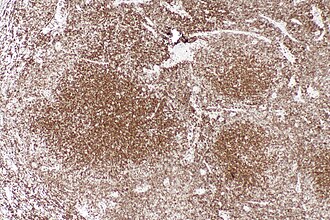

File:Follicular lymphoma - control bcl2 -- low mag.jpg

Normal BCL2 staining in a lymph node.